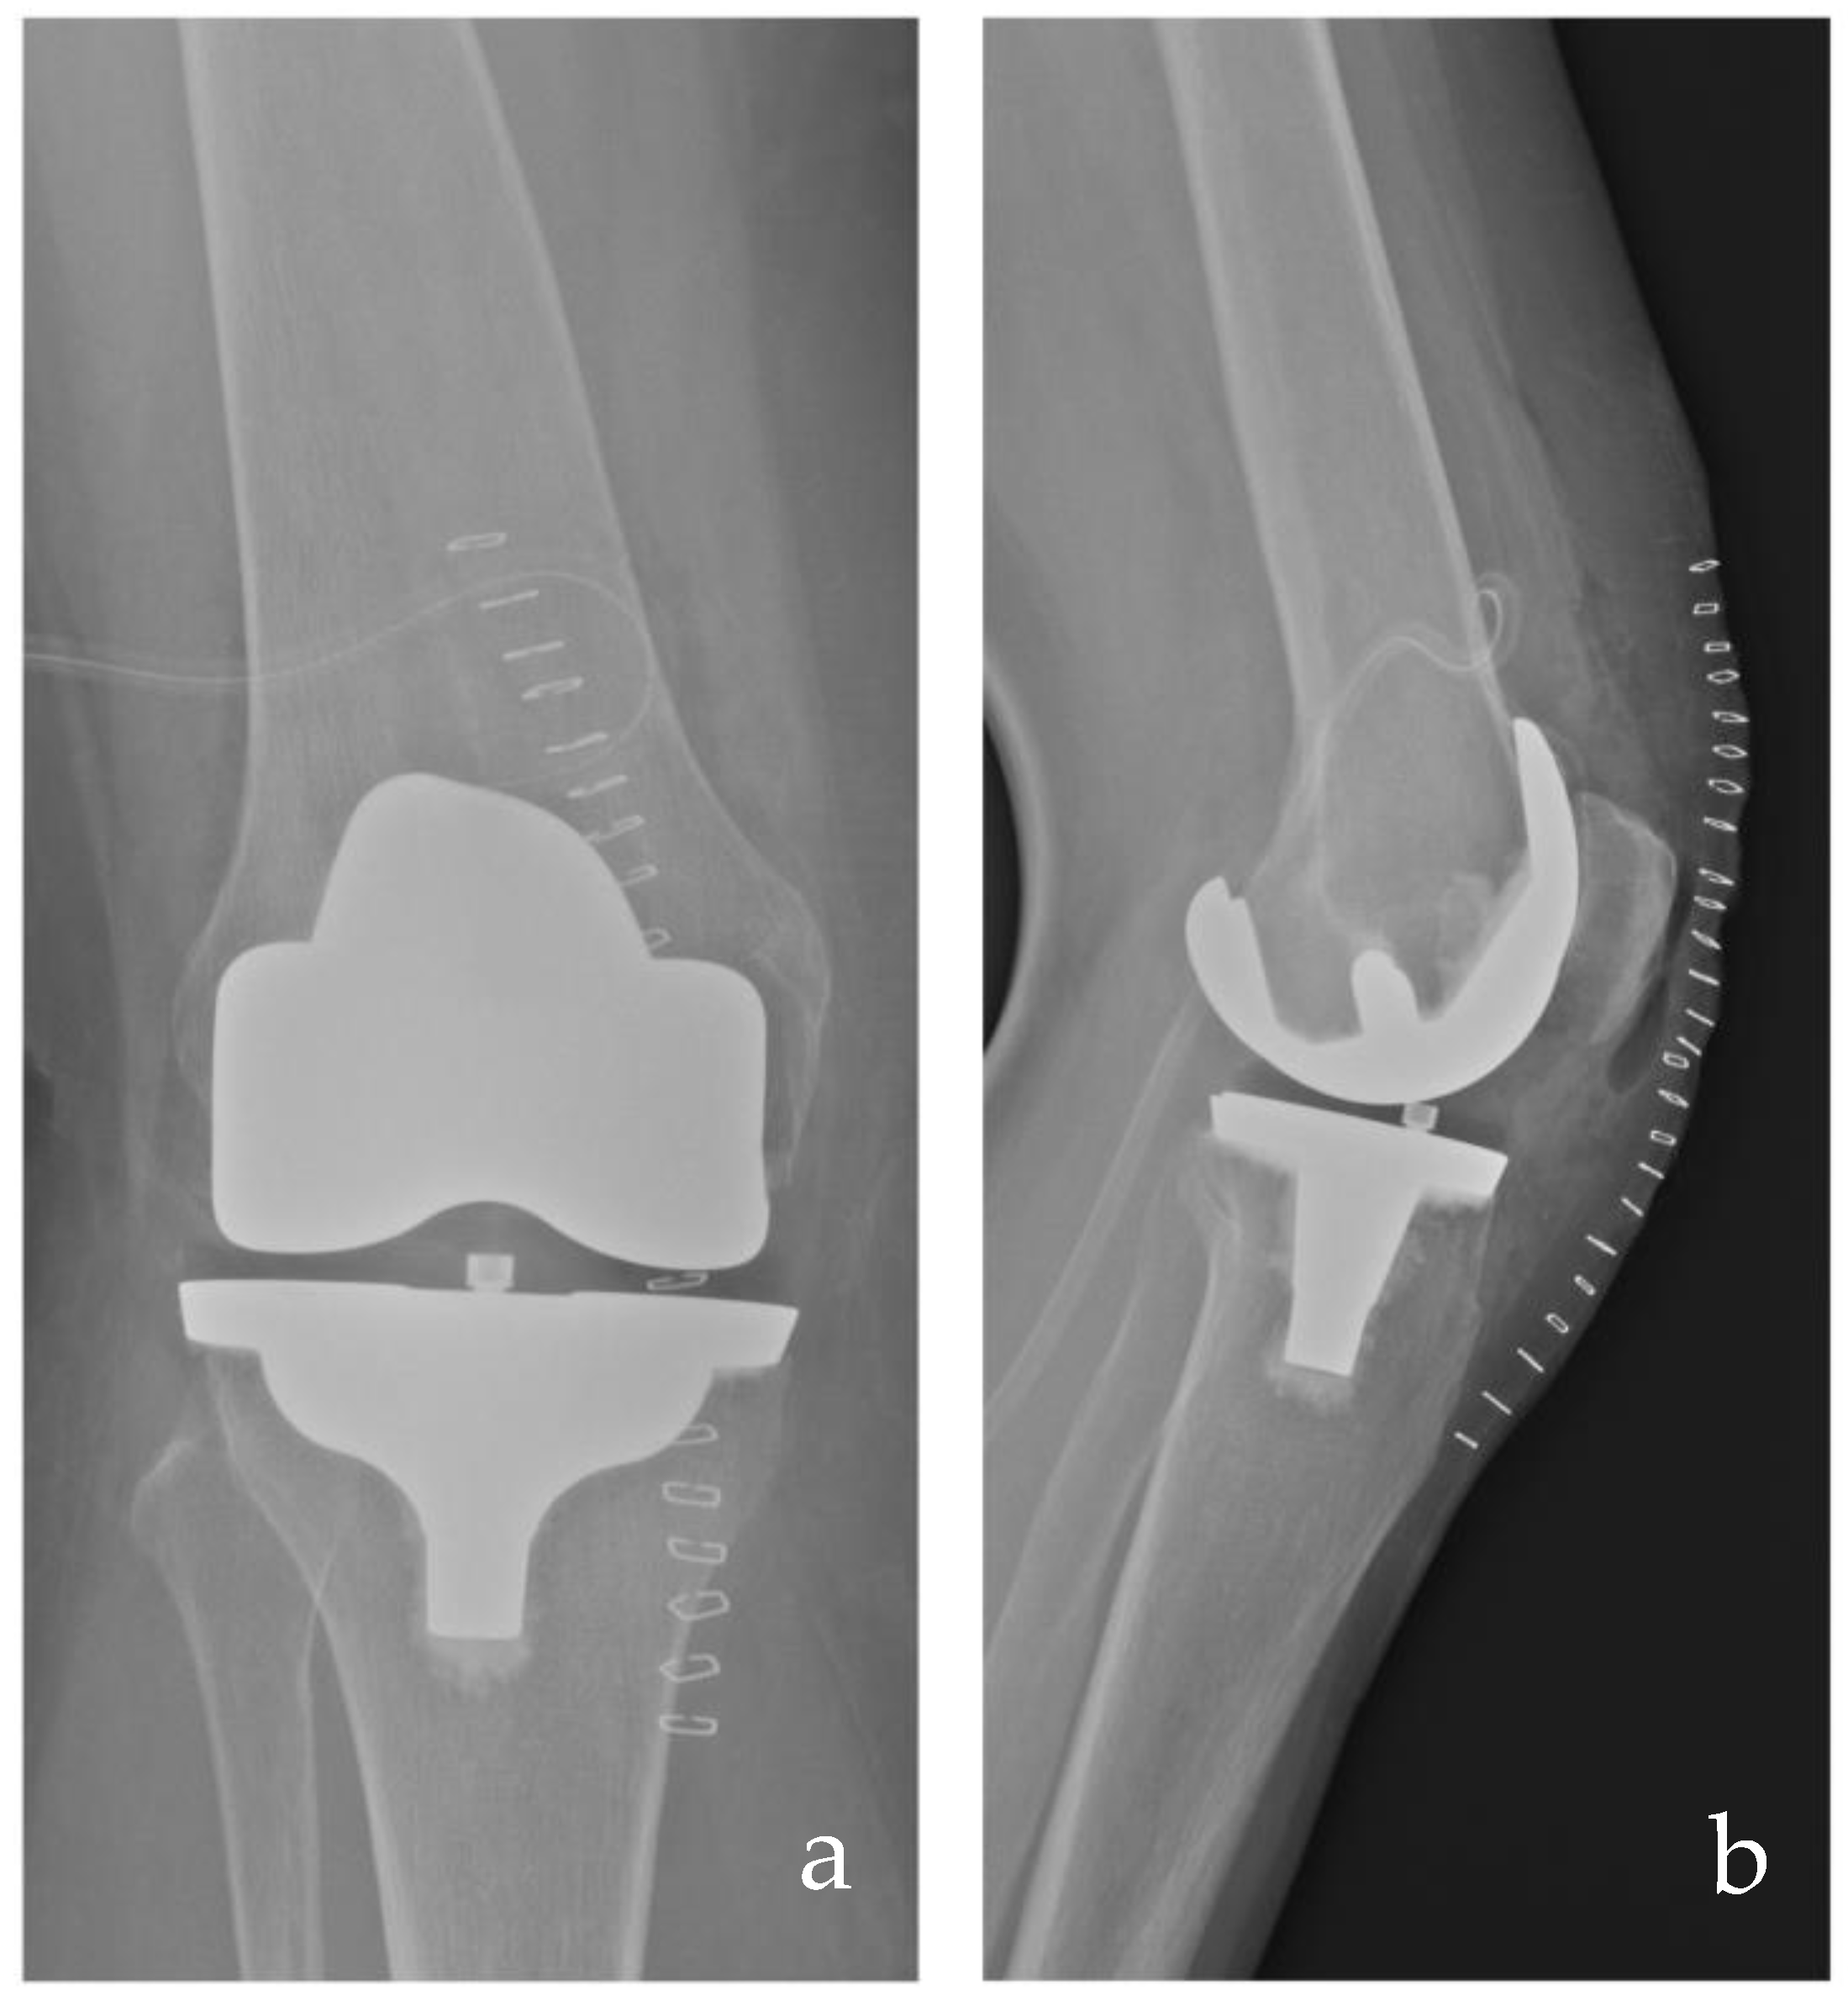

- Vecchini, E.; Ramazzini, L.; Lunardelli, E.; Zancanaro, F.; Amarossi, A.; Anselmi, A.; De Cristan, D.; Maluta, T.; Magnan, B.; Ricci, M. Short-Term Clinical and Radiological Comparisons between Two Medial Pivot Total Knee Arthroplasty Implants with Different Geometries. Acta Biomed. 2023, 94, e2023087–e2023094. [Google Scholar] [CrossRef]